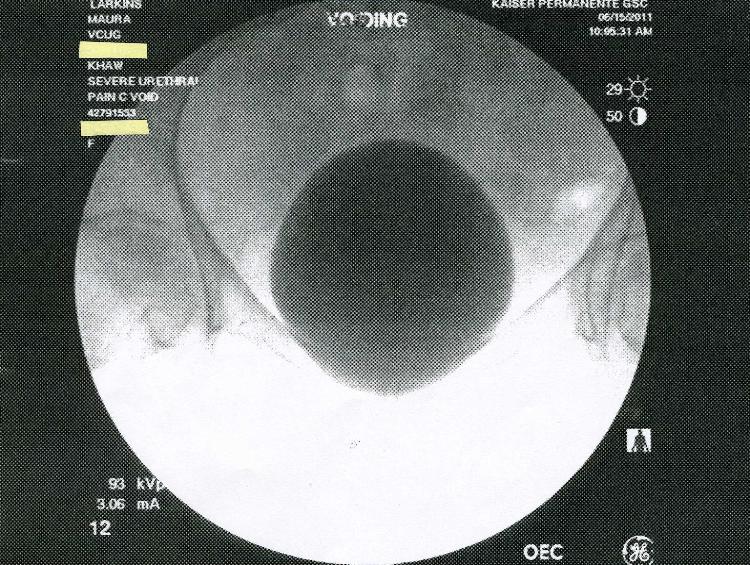

In July 2011 Kaiser Permanente in San Diego claimed that a large series of

X-rays done at the brand new Garfiled Specialty Center was not preserved on

film or saved electronically.  Kaiser claimed that only five images were

saved-on thermal paper! Below are the five images.  Incredibly, two of the

saved images are previews, or "scout" x-rays.  Why would these be printed

out?  They were not medically useful.  Answer: The truth is that all the images

were saved digitally, and Kaiser concealed them to cover-up an incorrect

diagnosis.